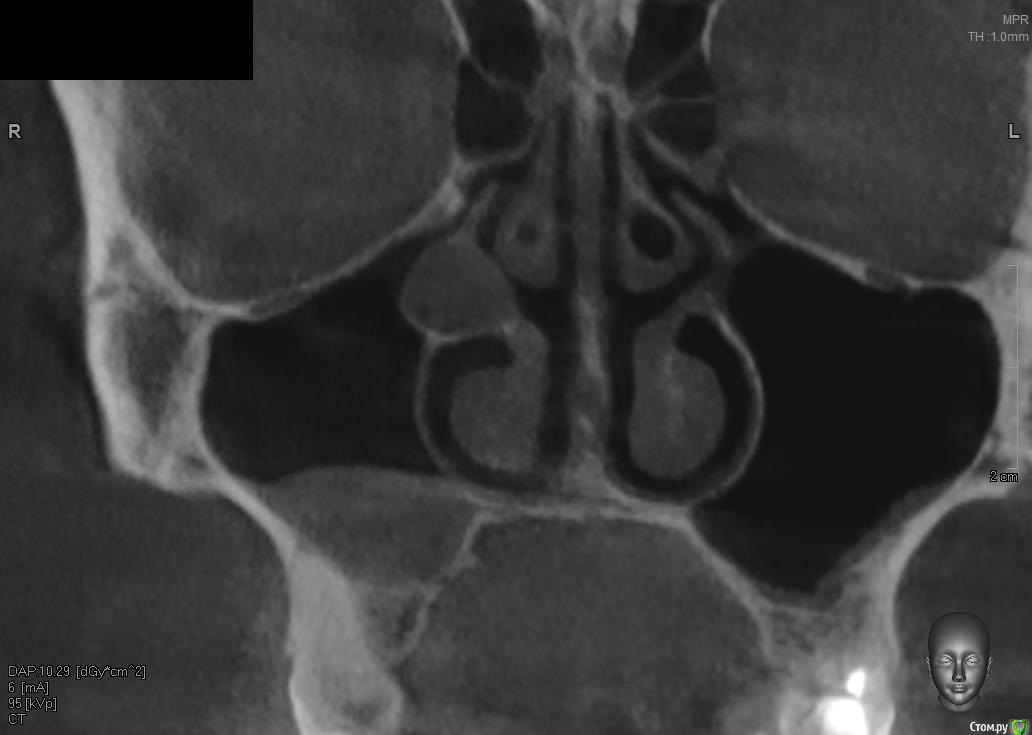

Павел7809 Опубликовано 26 сентября, 2017 Поделиться Опубликовано 26 сентября, 2017 Собственно делал кт для имплантации и наткнулся на нечто , чего не видел ранее и что меня смутило... Тактика? Ссылка на комментарий

Irouil Опубликовано 27 сентября, 2017 Поделиться Опубликовано 27 сентября, 2017 Речь не о дне пазухи. Под крючковидным отростком скорее всего полип, в любом случае это не по части имплантолога. Если пациент хочет - эндоскопом из носа достать, но жить пока, судя по всему, не мешает. Короче говоря - я бы синусил, ну а если пациент хочет - расчехлил бы камеру и выщипал из носа бяку. Если Вы этим не занимаетесь (судя по вопросу - нет) - предложите ему/ей консультацию лора. З.ы. конечно, это все вилами о воде - надо все кт смотреть. Я исхожу из того, что Вы нам показали самое интересное) Ссылка на комментарий

Павел7809 Опубликовано 27 сентября, 2017 Автор Поделиться Опубликовано 27 сентября, 2017 З.ы. конечно, это все вилами о воде - надо все кт смотреть. Я исхожу из того, что Вы нам показали самое интересное) По Кт ровный шарик. Стенки плотные(внутри жидкость?) Так как я перестраховщик да и вообще первый раз такое вижу - отправил к лорам на консультацию. Однажды, помню, вообще нашел случайно в пазухе железную дробину 4 мм диаметром... Ссылка на комментарий